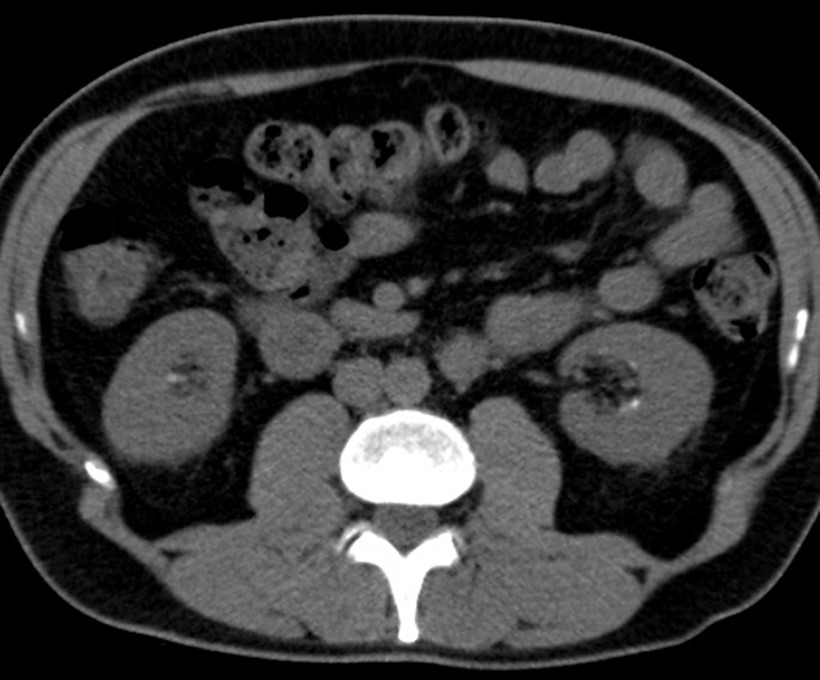

Πλάκες του Randall, αξονική τομογραφία

Η εναπόθεση αλάτων ασβεστίου στην κορυφή της νεφρικής θηλής ονομάζεται πλάκα του Randall. Πρόκειται για μια ενδοθηλιακή συσσώρευση φωσφορικού ασβεστίου το οποίο έχει περάσει μέσα από τη βασική μεμβράνη της αγκύλης του Henle. Η πλάκα τελικά διαβρώνει το ουροθήλιο και πάνω της εναποτίθενται άλατα φωσφορικού και οξαλικού ασβεστίου με τελικό αποτέλεσμα το σχηματισμό πέτρας.

Το γεγονός ότι το 50% των ασθενών με λιθίαση από CaOx έχουν εναπόθεση λίθου στην απόληξη της θηλής, ενισχύει την υπόθεση ότι οι πλάκες του Randall μπορεί να είναι ένα πρώιμο στάδιο της παθογένεσης των λίθων.